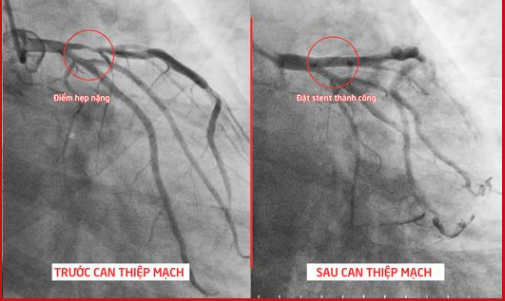

| Hình ảnh trước và sau can thiệp mạch của bệnh nhân L. Ảnh BVCC |

Kết quả cho thấy động mạch liên thất trước bị hẹp nặng, lên đến 95% (đây là 1 nhánh mạch máu rất lớn và quan trọng của tim) nguy cơ tử vong cao. Ekip bác sĩ khoa Tim mạch – Nội tiết đã nhanh chóng tiến hành can thiệp bằng cách nong bóng và đặt stent để khôi phục dòng máu, phủ toàn bộ tổn thương.

Sau 1 tiếng, Ekip đã đặt stent thành công, tổn thương được sửa chữa toàn bộ, dòng chảy trong lòng mạch máu nuôi tim được lưu thông tốt trở lại. Sau can thiệp, sức khỏe bệnh nhân ổn định, hết đau ngực hoàn toàn, các chỉ số xét nghiệm tốt. Dự kiến sau khoảng 2-3 ngày bệnh nhân sẽ được xuất viện.